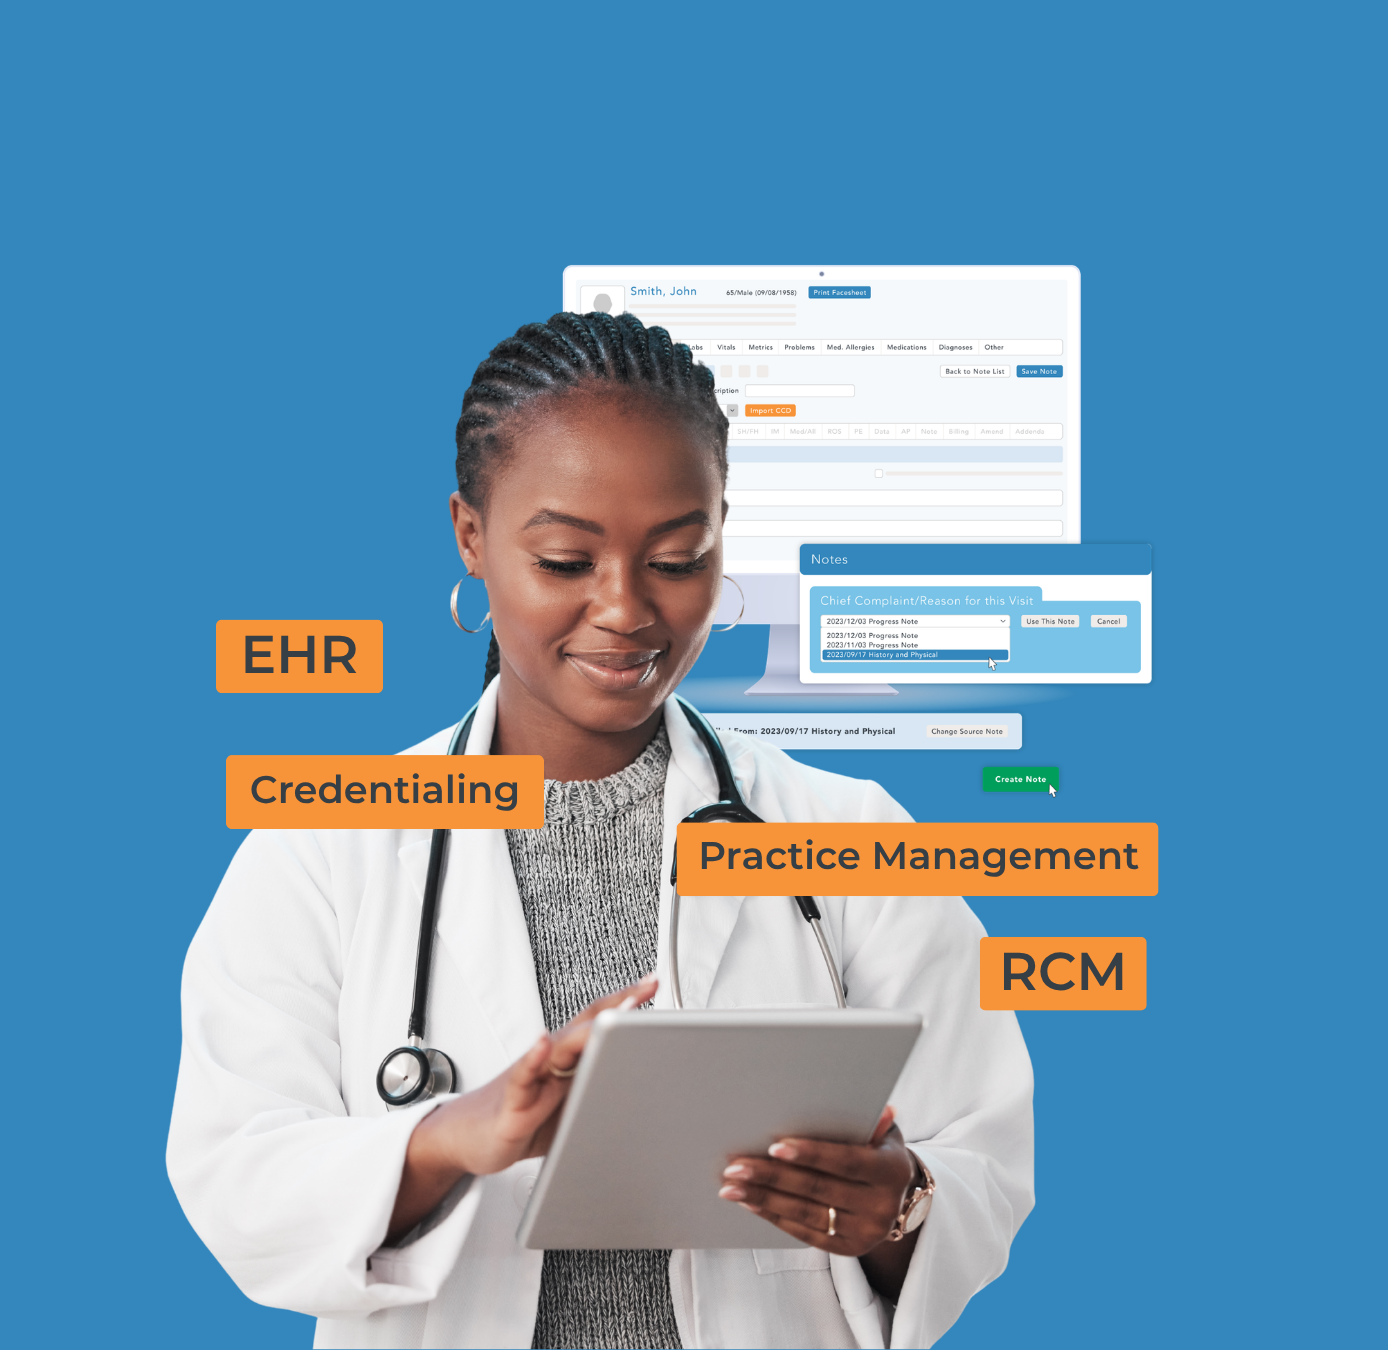

LivTech